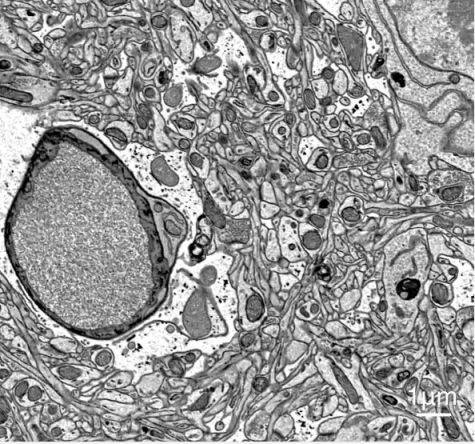

| Electron Optics | Resolution | 1.5 nm@1 kV SE | 1.8 nm@1 kV BSE | 1.5 nm@15 kV BSE |